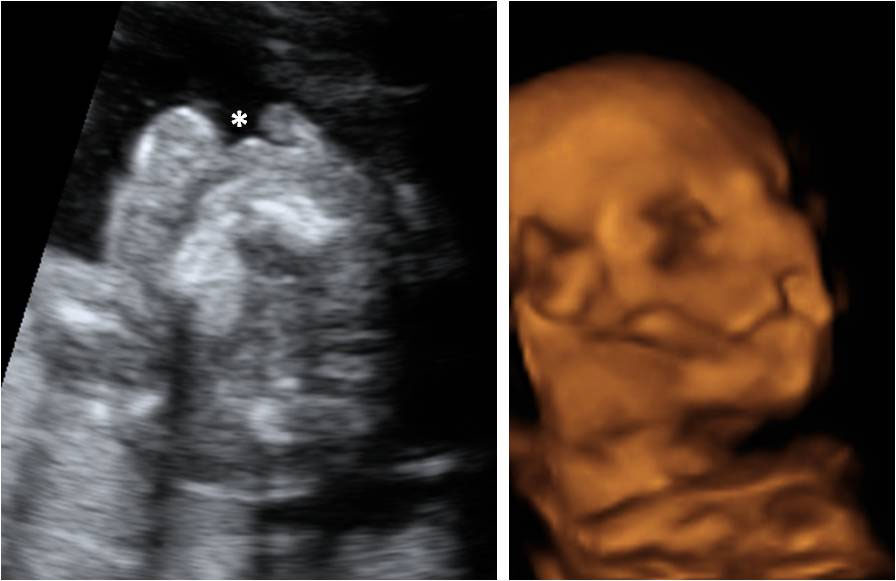

Las ecografías en 2D y en 3D en la semana 20 de embarazo permite diagnosticar algunas malformaciones congénitas fetales, como el labio leporino, que se visualiza en estas imágenes.

Labio leporino (*)

Visualización del mismo caso con ecografía 2D (izquierda) y con ecografía 3D (derecha). La imagen más evidente en la ecografía 3D hace más comprensible para los padres el alcance del problema.